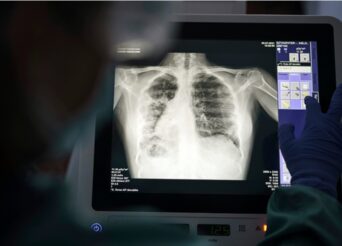

ΚΟΡΟΝΟΪOΣ: ΣΤΑ 2.130 ΤΑ ΚΡΟYΣΜΑΤΑ ΣHΜΕΡΑ, 323 ΔΙΑΣΩΛΗΝΩΜEΝΟΙ, 47 ΝEΟΙ ΘAΝΑΤΟΙ

Τα νέα κρούσματα κορονοϊού που εντοπίστηκαν στη χώρα το τελευταίο 24ωρο είναι 2.130, όπως ανακοίνωσε ο ΕΟΔΥ. Ο αριθμός των διασωληνωμένων ασθενών Covid είναι 323, από τους οποίους οι 292 είναι ανεμβολίαστοι ή μερικώς εμβολιασμένοι και οι 31 είναι πλήρως εμβολιασμένοι. Οι νέοι θάνατοι που ανακοινώθηκαν είναι 47. Αναλυτικά, όπως ανακοινώθηκε από τον ΕΟΔΥ, τα νέα εργαστηριακά επιβεβαιωμένα […]